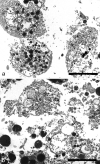

Chondrocyte apoptosis is known to contribute to articular cartilage damage in osteoarthritis and is correlated to a number of cartilage disorders. Micromass cultures represent a convenient means for studying chondrocyte biology, and, in particular, their death. In this review, we focused the different kinds of chondrocyte death through a comparison between data reported in the literature. Chondrocytes show necrotic features and, occasionally, also apoptotic features, but usually undergo a new form of cell death called Chondroptosis, which occurs in a non-classical manner. Chondroptosis has some features in common with classical apoptosis, such as cell shrinkage, chromatin condensation, and involvement, not always, of caspases. The most crucial peculiarity of chondroptosis relates to the ultimate elimination of cellular remnants. Independent of phagocytosis, chondroptosis may serve to eliminate cells without inflammation in situations in which phagocytosis would be difficult. This particular death mechanism is probably due to the unusual condition chondrocytes both in vivo and in micromass culture. This review highlights on the morpho-fuctional alterations of articular cartilage and focus attention on various types of chondrocyte death involved in this degeneration. The death features have been detailed and discussed through in vitro studies based on tridimensional chondrocyte culture (micromasses culture). The study of this particular mechanism of cartilage death and the characterization of different biological and biochemical underlying mechanisms can lead to the identification of new potentially therapeutic targets in various joint diseases.